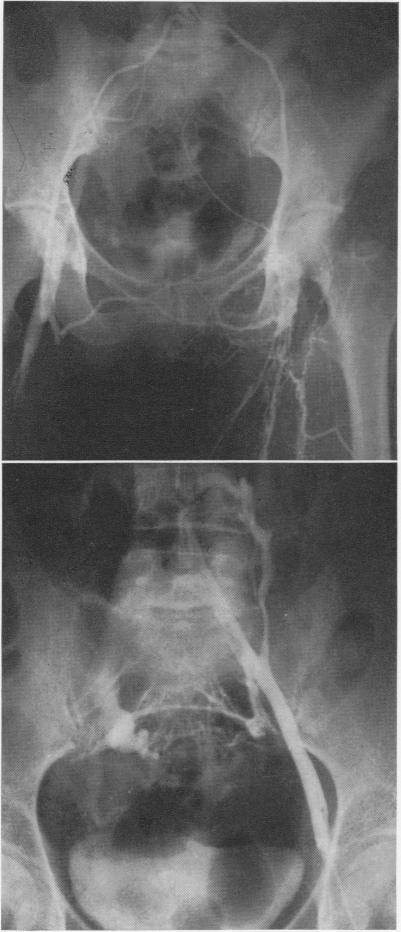

Iliofemoral venous thrombosis. Reappraisal of thrombectomy.

Ann Surg. 1970 Jun;171(6):961-70. doi: 10.1097/00000658-197006010-00018.